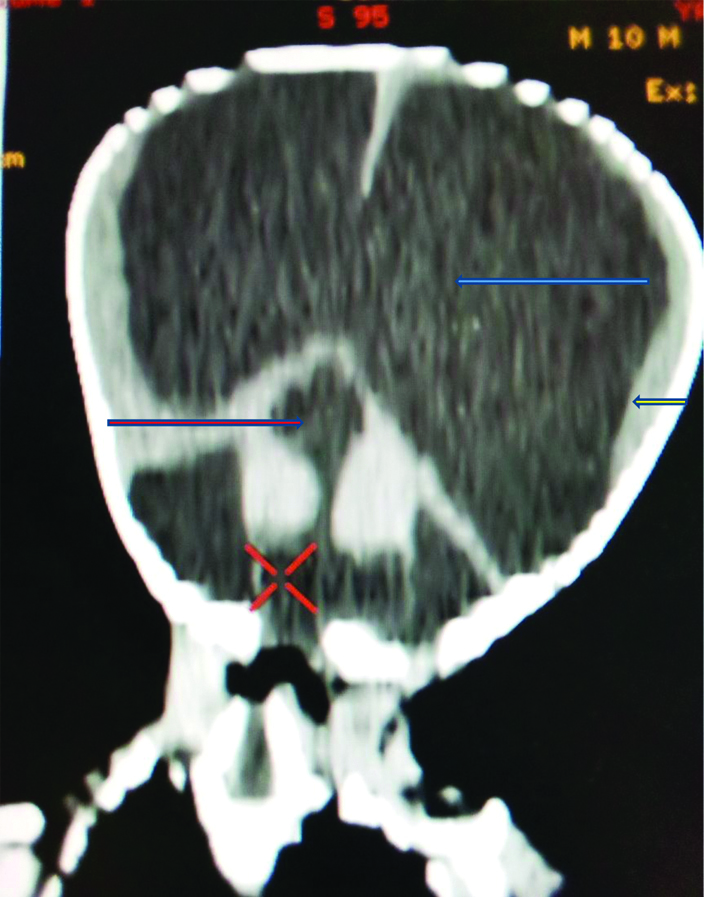

Reconstructed coronal computed brain tomogram showing dilated lateral ventricles (blue arrow), thinned cerebral mantle (yellow arrow), dysplastic fourth ventricle communicating with the posterior fossa cyst giving the key hole deformity (red arrow).